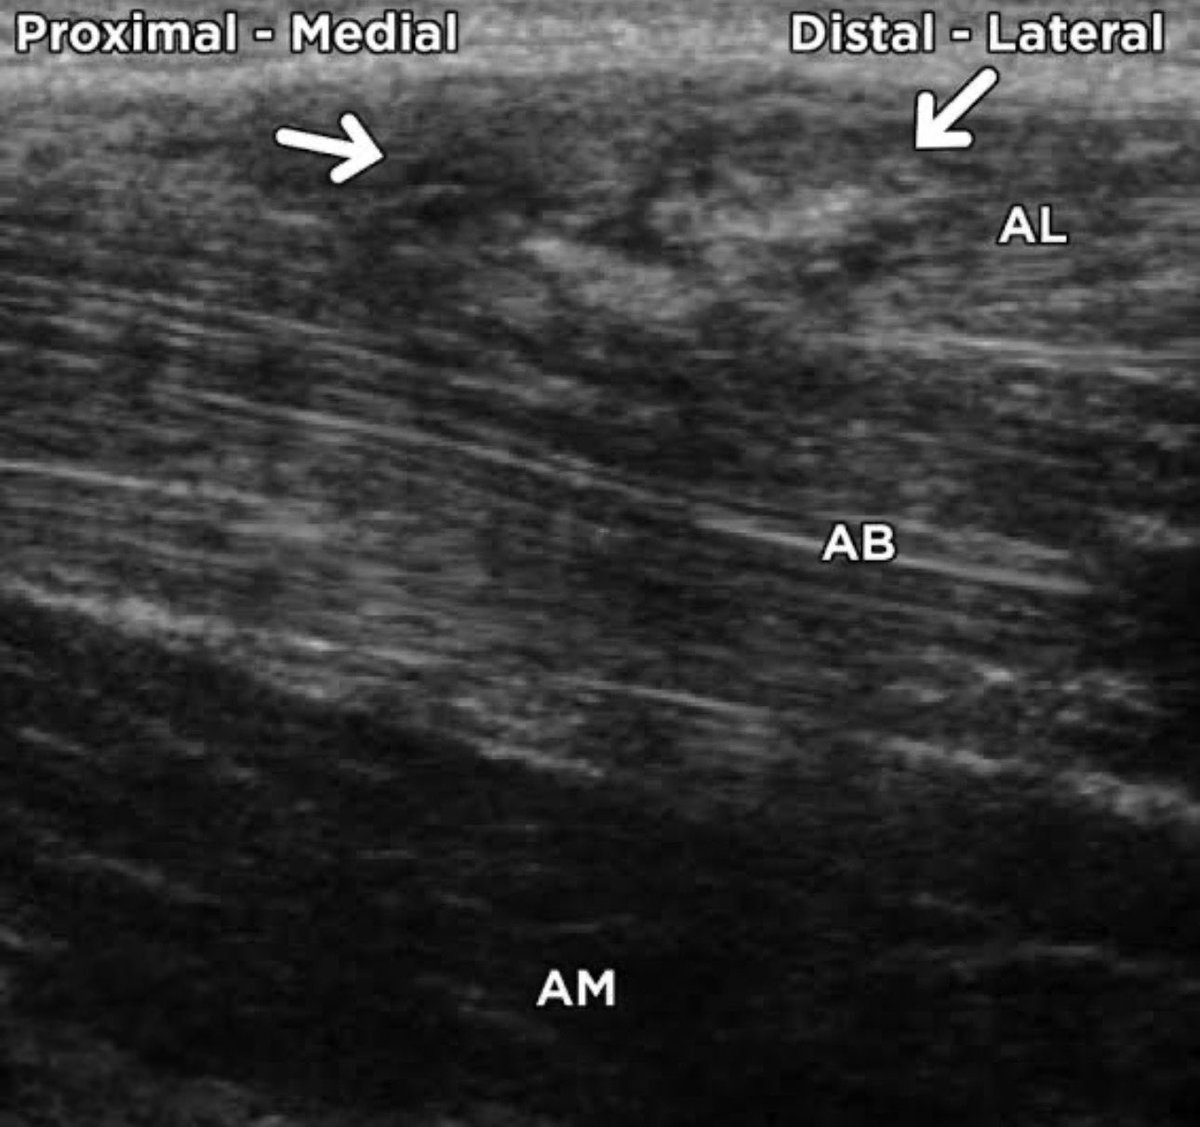

🔸דירוג הפציעה(לפי מיקום וחומרת הקרע): רוב פציעות המפשעה הן פציעות המשקפות עומס ויתרחשו בשריר ה- Adductor Longus באיזור המעבר בין סיבי שריר לגיד. דרגה1- קרע חלקי ומצומצם שמסב כאב אך ללא ירידה בכח/בתנועה. דרגה2- קרע חלקי עם כאב, נפיחות וגם הפרעה ביציבות ובתנועה. דרגה3- קרע מלא

🔸שריר המפשעה(המקרבים) הוא למעשה מקלעת שרירים(שישה לשם הדיוק). הם מחברים את עצם האגן לירך, ממוקמים בין ההמסטרינג האחורי לארבע ראשי הקדמי, ומשתתפים בכלל תנועות מפרק הירך ובעיקר מבצעים את תנועת הצמדת הירך מהחוץ בחזרה פנימה אל קו האמצע. בכדורגל החשיבות המרכזית היא בייצוב שתי הרגליים

3/2/26 פציעת קני סייף - מתיחה/קרע במפשעה (Adductor Longus) הקשר נפצע במשחק הגביע מול כפר קאסם. המועדון הוציא מוקדם יותר הערב הודעה קצרה ומעריך את זמן החזרה בכ-3 שבועות. לא נמסרו פרטים באיזו רגל מדובר, מיקום ודרגת הקרע. מה משמעות הפציעה ומה ניתן ללמוד מהערכת זמן ההחלמה? 🔻🔻